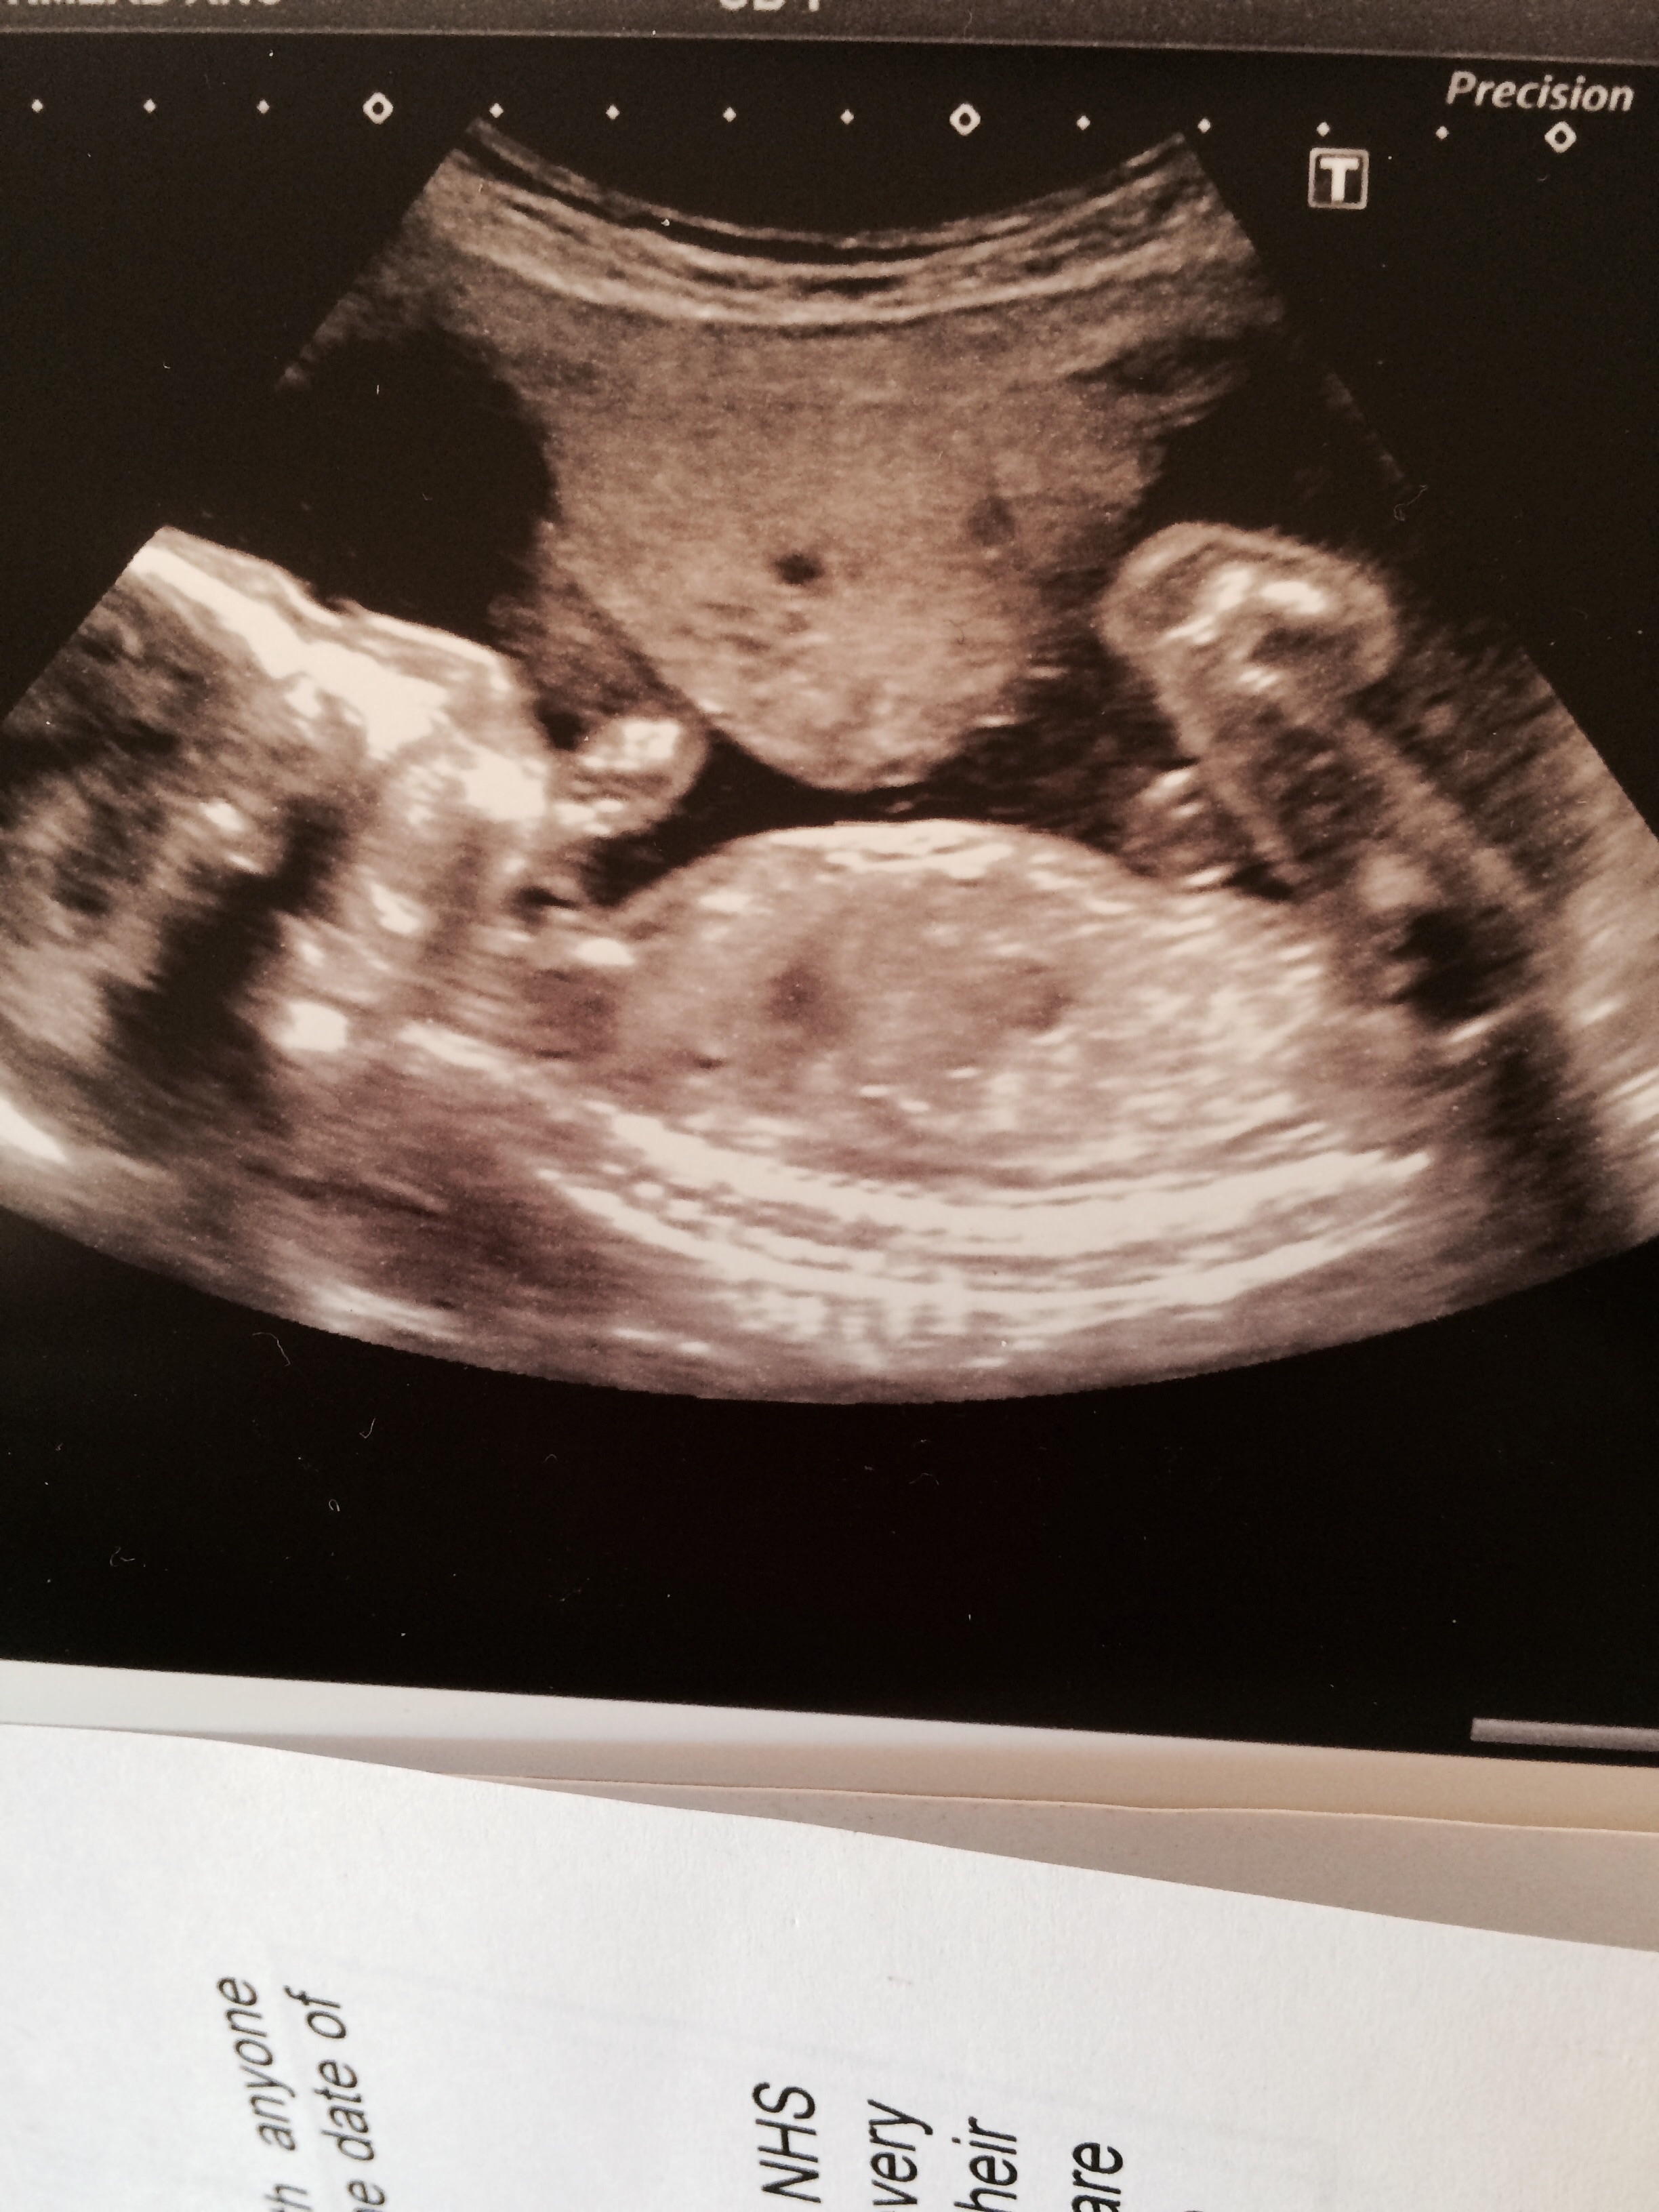

Hey all! Would be really grateful for your help! Having looked through hundreds of nub pics I'm sure there is a nub in front of the leg. I have seen many like it and people have commented on gender but on a few other sites most have said you can't see the nub. I would be most grateful for your opinion! Thank you! Pic is at 12+4 by scan but 11+5 by dates.